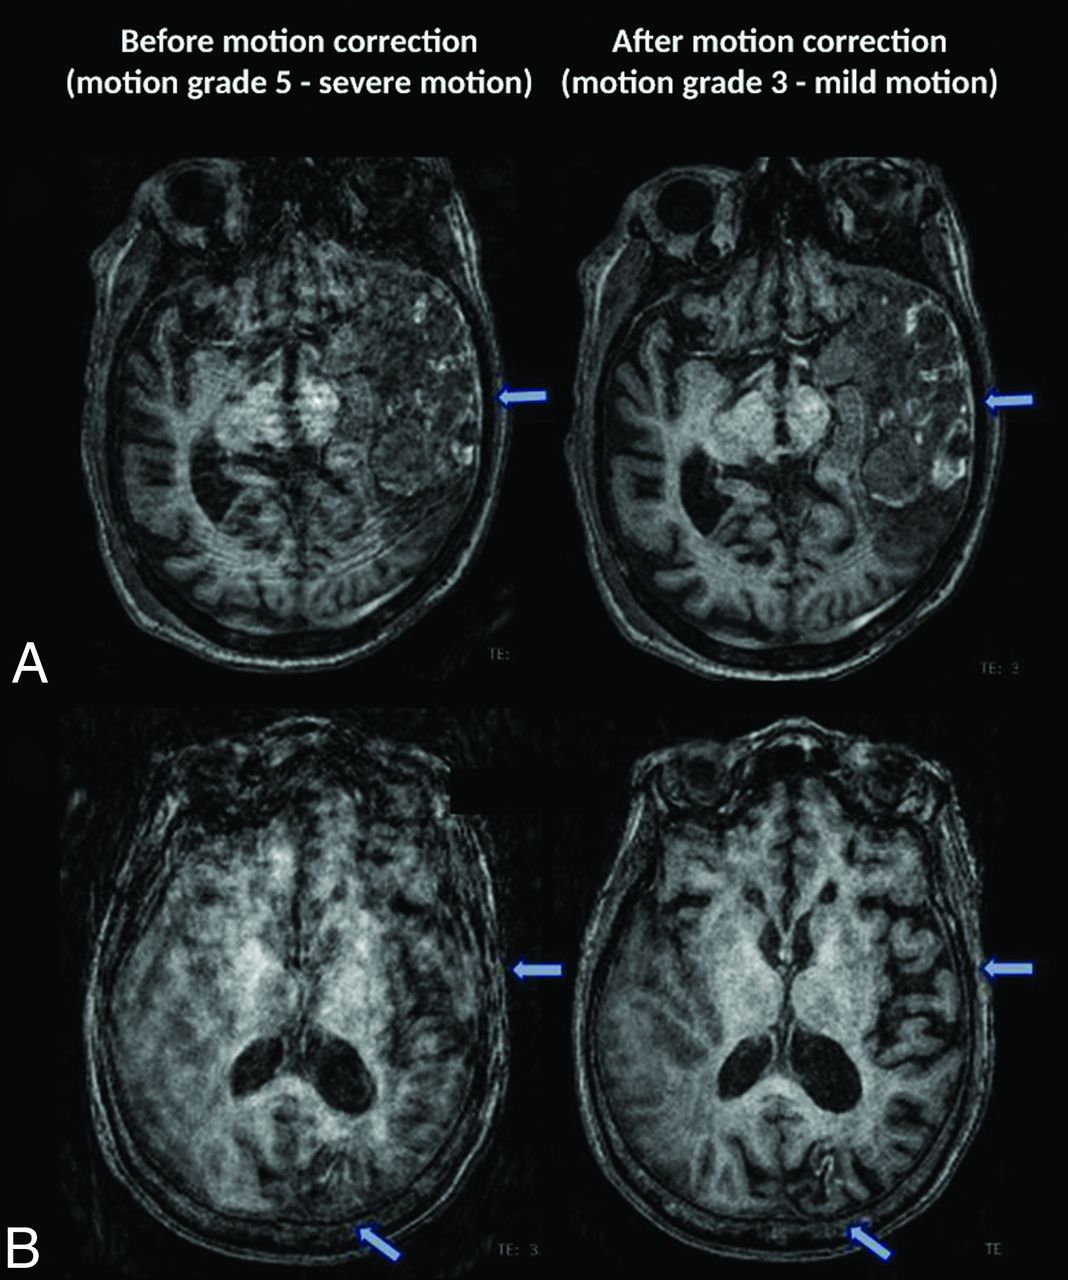

Among the 5 cases with baseline no motion (motion grade 1), there was no change in the motion grade after SAMER motion correction. Of the 46 cases with minimal motion (motion grade 2), most cases (78%) showed no change in motion grade, while motion artifacts worsened by 1 grade in 8 cases (17%) and improved in 2 cases (4%). The Online Supplemental Data show an example of a case with minimal motion (grade 2) at baseline that worsened to mild motion (grade 3) on SAMER motion correction. Note that the degree of motion in the SAMER motion-corrected images is still quite small and did not compromise the diagnostic quality of the image. In 30 cases with baseline mild motion (motion grade 3), there was no change in the motion grade for 19 cases (63%) and improvement in 11 cases (37%). Representative side-by-side comparison of baseline and SAMER motion-corrected images are provided in Fig 2.

Sagittal T1 MPRAGE images illustrating examples of cases with motion artifacts (grades I–5) for which SAMER reconstruction improved motion by 1 grade. A, A 23-year-old woman with a normal brain. B, Postoperative findings from resection of a left parietal lobe tumor in a 59-year-old woman with a history of anaplastic oligodendroglioma. C, Diffuse parenchymal volume loss with disproportionate involvement of the frontal and parietal lobes and, to a lesser extent, the left temporal lobe in a 59-year-old man with history of cognitive impairment. D, An 83-year-old woman with history of chronic cerebral small-vessel disease. E, Expected postoperative changes and enhancement from left temporal parietal craniotomy (arrows) are demonstrated in a 63-year-old man with history of glioblastoma.

In baseline nondiagnostic cases of moderate or severe motion (motion grades 4 or 5, respectively), SAMER motion correction reduced motion artifacts in 87.5% (14/16) of cases (Fig 3), which included 100% of moderate motion cases (grade 4) and 75% of severe motion cases (grade 5). In fact, 11 of the 16 nondiagnostic grade cases (69%) were considered diagnostic in quality after SAMER motion correction, ie, they were reduced from a score of 4 or 5 to a score of ≤3. Representative images comparing cases with severe motion before and after SAMER motion correction are provided in Fig 4. For cases with minimal, mild, moderate, and severe motion, SAMER improved the motion grade by an average 0.13 (SD, 0.7), 0.3 (SD, 0.5), 1.1 (SD, 0.25), and 1.1 (SD, 0.83) grades, respectively (Table 2).